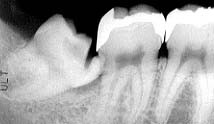

「右下の親知らずが痛たくって! 何とかして下さい」

初診時口腔内およびX線所見:

3本残った親知らずはいずれも虫歯で、いずれも抜歯が必要と思われるがそれ以外の歯に 関しては問題なく、清掃状態も比較的良好。 右側下顎智歯周辺の歯肉は腫脹しており、レントゲンでは歯冠の一部を切断した痕跡が 明瞭に確認された。

処置および経過:

排膿を図るために麻酔をしたところ、激しい疼痛の原因が歯髄の急性炎症であったためか 疼痛が治まり抜歯も可能な状態と判断して早急に抜歯を行った。 抜歯後の予後は良好で特に問題なし。

考察:

疼痛が著しく麻酔が効きにくい場合には、通常排膿と投薬を行って炎症の緩和を待って 2〜3日後に改めて抜歯を行うケースが多い。本症例のように歯髄炎末期の疼痛で、 周囲歯肉の炎症が軽度で十分な麻酔効果が得られた場合にはなるべく早く抜歯 した方が良いものと思われる。 前医で抜歯を試みた時には周囲の炎症が著しく歯冠の切断も困難だったものと思われるが、 歯冠の切断をもっと確実に行っていれば楽に抜歯できたのでは…?